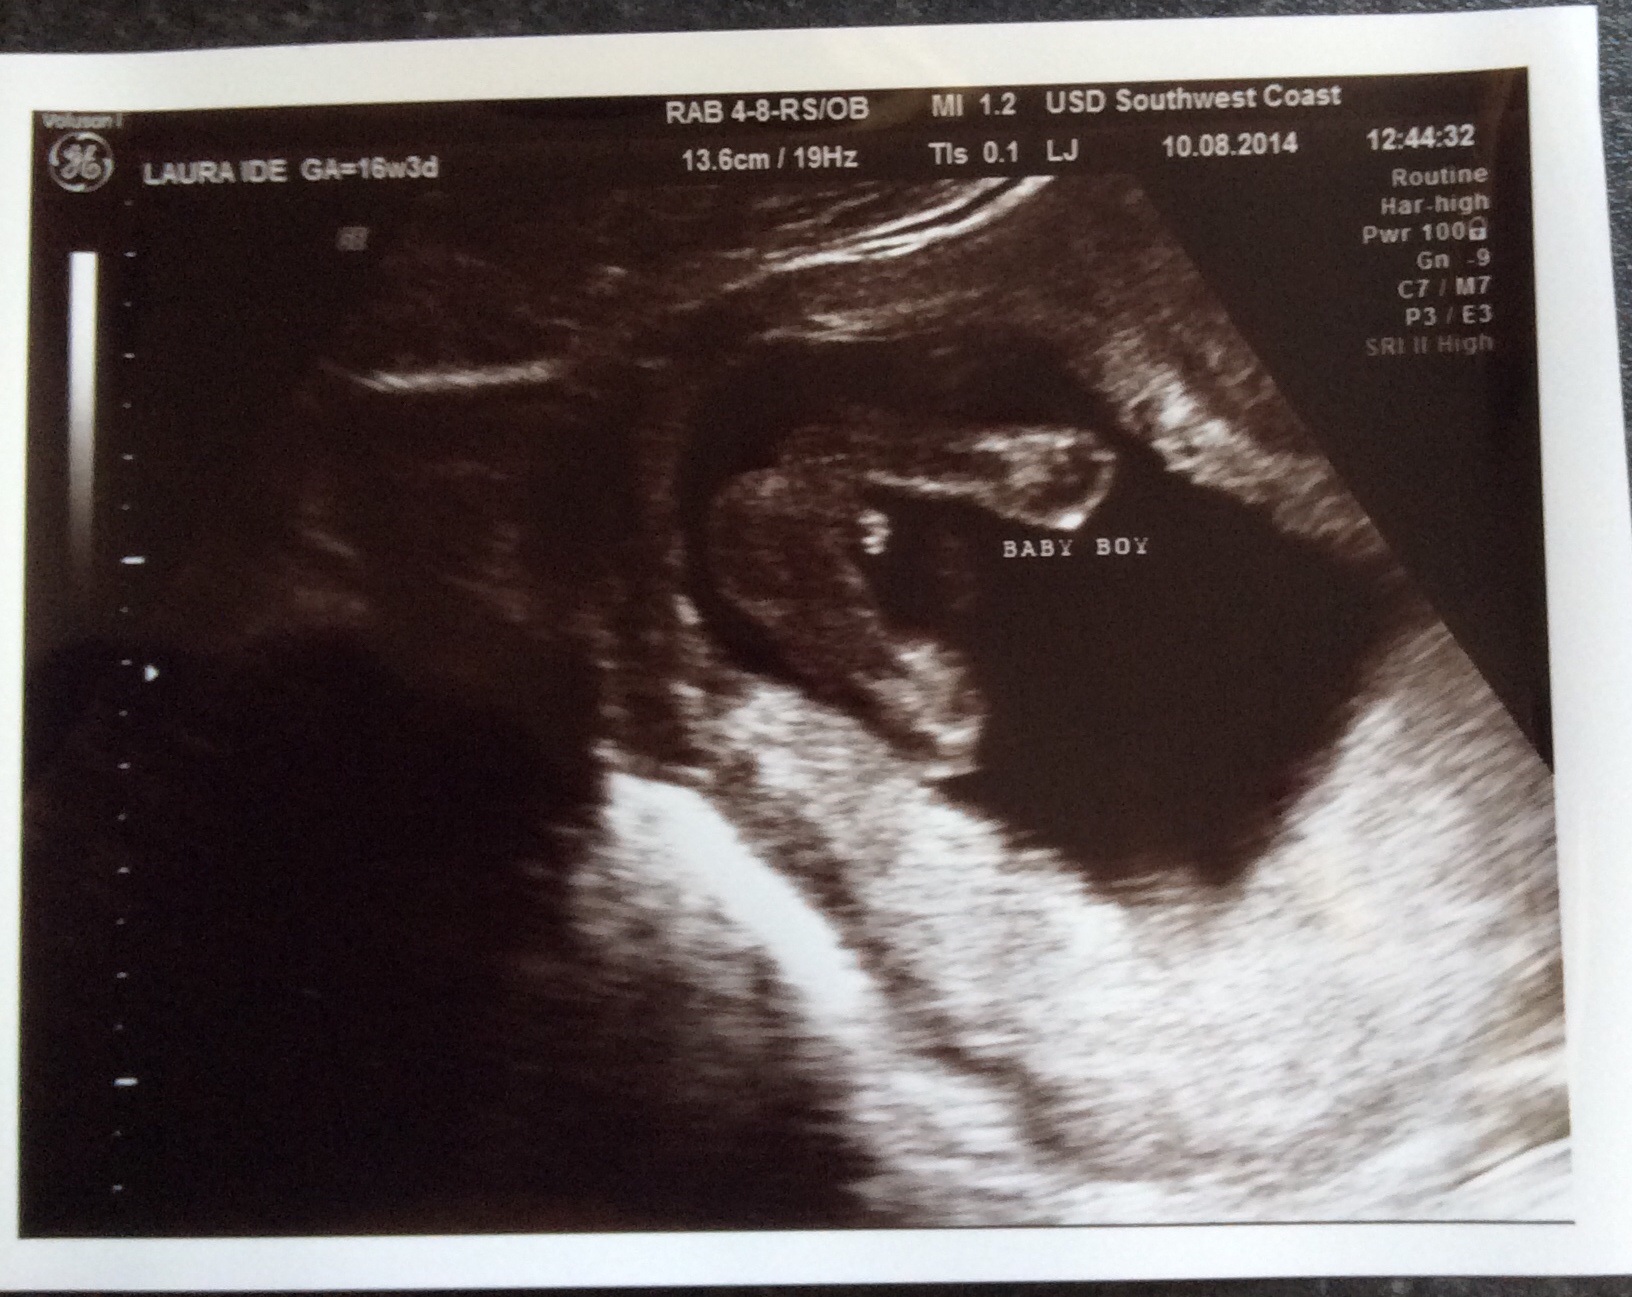

Been told boy but potty shot 16+3 I'm not so sure??

When we got called back in she had another look but still struggled she was saying I'm going to have to get you back in, then she got a picture and said boy! We have 3 photos all together?

I don't think it looks anything like a boy but I am by no means an expert! With our son his 16w gender scan was a clear turtle it was no mistakable at all so I kind of knew what I was looking for!

Through the whole scan me and hubby didn't catch site of any boy bits and were so shocked when she said boy! I just wondered what you guys thought? If it is then that's fine and I will except that I'm having boy number 5 but just don't want to think I'm having a boy choose his name and it be a girl, I need to know so I can bond with the baby!

Anyways this is the scan potty shoots! The first one she said was boy